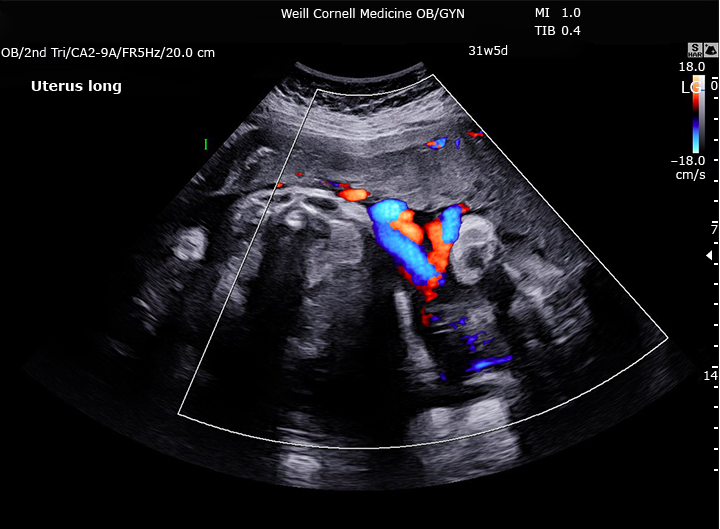

Cordones umbilicales entrelazados con dos diferentes latidos que tipo de embarazo multiple sugiere

monoamniotic